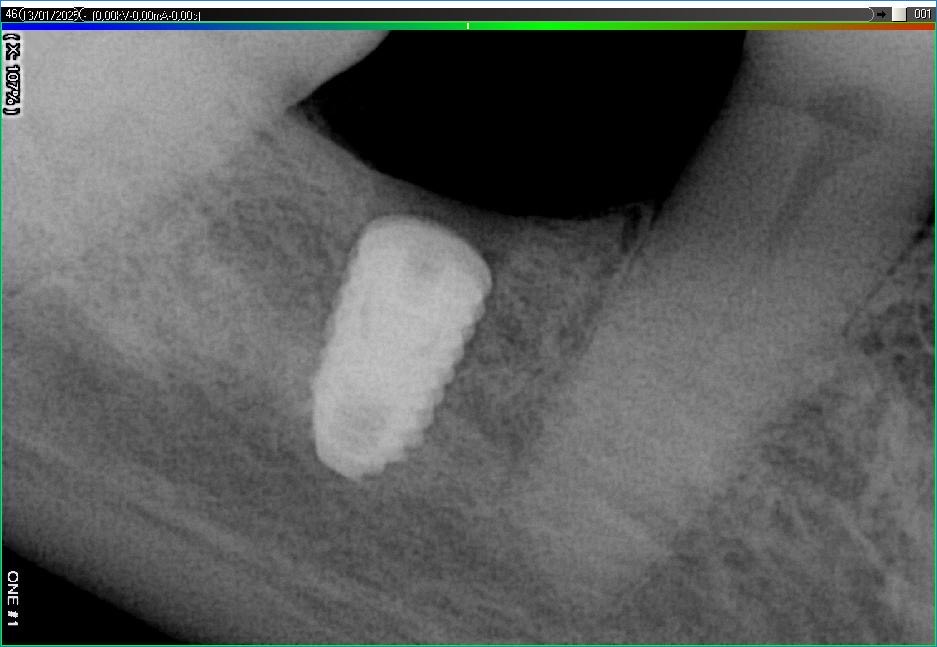

Імплантація